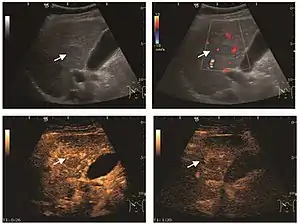

US examination is required to detect liver metastases in patients with oncologic history. In addition, the method can incidentally detect metastases in asymptomatic patients. Early identification (small sizes, small number) is important to establish an optimal course of treatment which can be complex (chemotherapy, radiofrequency ablation, surgical resection) but welcomed. In addition, discrimination of synchronous lesions that have a different nature is also important knowing that up to 25–50% of liver lesions less than 2 cm detected in cancer patients may be benign . US sensitivity for metastases detection varies depending on the examiner's experience and the equipment used and ranges between 40 and 80% . Sensitivity is conditioned by the size and acoustic impedance of the nodules. For a lesion diameter below 10 mm US accuracy is greatly reduced, reaching approx. 20%. Other elements contributing to lower US performance are: excessive obesity, fatty liver disease, hypomobility of the diaphragm, and certain patterns of hyperechoic or isoechoic metastases that can be overlooked or can mimic benign conditions. Conventional US appearance of metastases is uncharacteristic, consisting of circumscribed lesions, with clear, imprecise or "halo" delineation, with homogeneous or heterogeneous echo pattern. They can be single (often liver metastases from colonic neoplasm) or multiple. Echogenity is variable. When increased, they can compress the bile ducts (which may be dilated) and the liver vessels. Liver involvement can be segmental, lobar or generalized. In this situation a pronounced hepatomegaly occurs. Generally, metastases have non-characteristic Doppler vascular pattern, with few exceptions (carcinoid metastases). Cyst-adenocarcinoma metastases due to semifluid content may have a transonic appearance. When increasing, they can result in central necrosis. CEUS examination is a real breakthrough for detection and characterization of liver metastases.

Increased performance is based on identifying specific vascular patterns during the arterial phase and seeing metastases in contrast to normal liver parenchyma during the sinusoidal phase. CEUS increased accuracy is due to the different behavior of normal liver parenchyma (captures CA in Kuppfer cells) against tumor parenchyma (does not contain Kuppfer cells, therefore CEUS appearance is hypoechoic). To this adds the particularities of intratumoral circulation represented by a reduced arterial bed compared to that of the surrounding normal liver and the absence of the portal vessels . In terms of vascularity, metastases can be hypovascular (in gastric, colonic, pancreatic or ovarian adenocarcinomas) with hypoechoic pattern during arterial phase, and similar during portal venous and late phases, respectively hypervascular (neuroendocrine tumors, malignant melanoma, sarcomas, renal, breast or thyroid tumors) with hyperechoic appearance during arterial phase, with washout during the portal venous phase and hypoechoic pattern 30 seconds after injection.